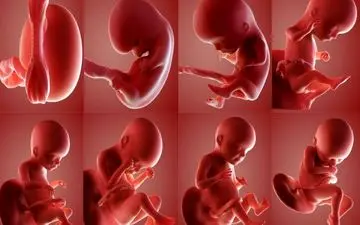

اگر میخواهید در مورد جنسیت جنین خود زودتر از موعد آگاه شوید متن زیر را بخوانید.

با پیشرفت تکنولوژی در حال حاضر، تعیین جنسیت جنین به روشهای بسیار دقیق و سریعی انجام میشود، با این حال برای تشخیص…